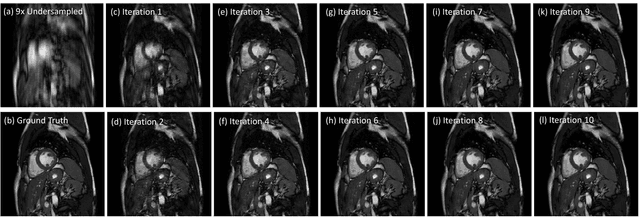

Abstract:Accelerating the data acquisition of dynamic magnetic resonance imaging (MRI) leads to a challenging ill-posed inverse problem, which has received great interest from both the signal processing and machine learning community over the last decades. The key ingredient to the problem is how to exploit the temporal correlation of the MR sequence to resolve the aliasing artefact. Traditionally, such observation led to a formulation of a non-convex optimisation problem, which were solved using iterative algorithms. Recently, however, deep learning based-approaches have gained significant popularity due to its ability to solve general inversion problems. In this work, we propose a unique, novel convolutional recurrent neural network (CRNN) architecture which reconstructs high quality cardiac MR images from highly undersampled k-space data by jointly exploiting the dependencies of the temporal sequences as well as the iterative nature of the traditional optimisation algorithms. In particular, the proposed architecture embeds the structure of the traditional iterative algorithms, efficiently modelling the recurrence of the iterative reconstruction stages by using recurrent hidden connections over such iterations. In addition, spatiotemporal dependencies are simultaneously learnt by exploiting bidirectional recurrent hidden connections across time sequences. The proposed algorithm is able to learn both the temporal dependency and the iterative reconstruction process effectively with only a very small number of parameters, while outperforming current MR reconstruction methods in terms of computational complexity, reconstruction accuracy and speed.

Abstract:Inspired by recent advances in deep learning, we propose a framework for reconstructing dynamic sequences of 2D cardiac magnetic resonance (MR) images from undersampled data using a deep cascade of convolutional neural networks (CNNs) to accelerate the data acquisition process. In particular, we address the case where data is acquired using aggressive Cartesian undersampling. Firstly, we show that when each 2D image frame is reconstructed independently, the proposed method outperforms state-of-the-art 2D compressed sensing approaches such as dictionary learning-based MR image reconstruction, in terms of reconstruction error and reconstruction speed. Secondly, when reconstructing the frames of the sequences jointly, we demonstrate that CNNs can learn spatio-temporal correlations efficiently by combining convolution and data sharing approaches. We show that the proposed method consistently outperforms state-of-the-art methods and is capable of preserving anatomical structure more faithfully up to 11-fold undersampling. Moreover, reconstruction is very fast: each complete dynamic sequence can be reconstructed in less than 10s and, for the 2D case, each image frame can be reconstructed in 23ms, enabling real-time applications.